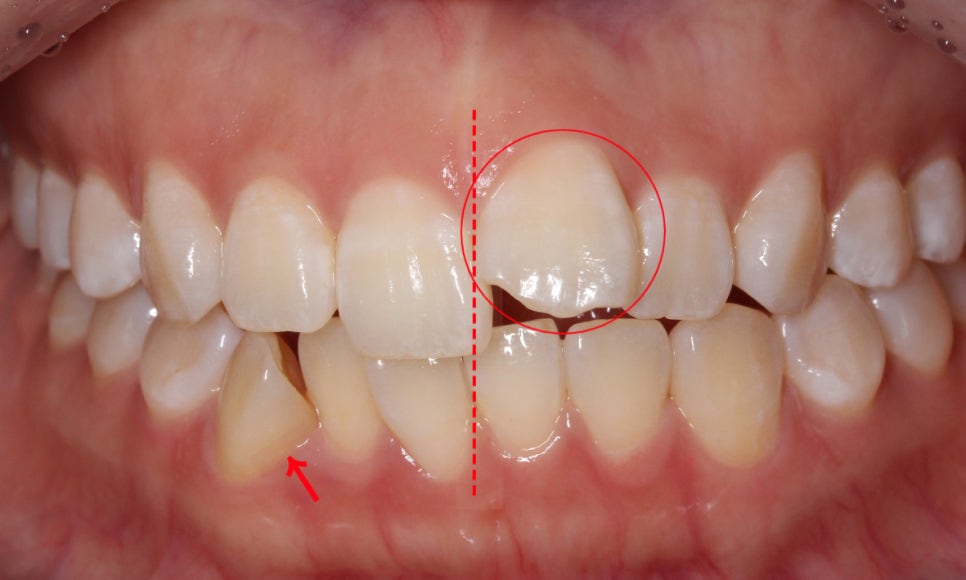

정면 구내사진을 보시면 위와 같이

상악과 하악을 교합하였을 때

전치부의 치아들이 제대로 교합되지 못하는 모습인데요,

상악 전치부의 경우 21번 중절치가 위쪽으로 들려있는 모습으로

덧니라고는 보기 어렵지만 앞니돌출 이 있는 모습입니다.

하악의 경우에는 전치부 치아들이 한쪽 방향으로

쏠려 있는 모습을 확인할 수 있는데요,

안모의 midline을 기준으로 좌측을 향해

삐뚤어져 있는 모습입니다.